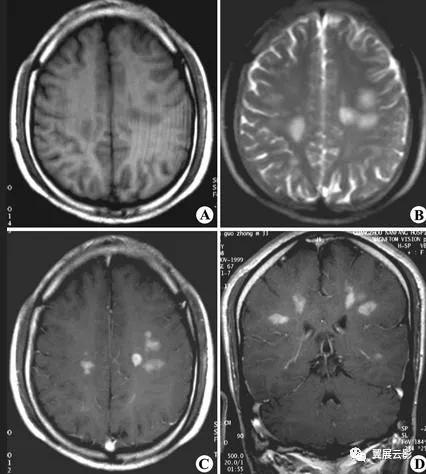

病例1:多发脑转移瘤

MR平扫转移瘤多呈等T1或长T1,等T2或长T2信号,瘤体内囊变坏死区呈明显长T1长T2信号,个别具有顺磁效应的转移瘤如黑色素瘤可出现短T1短T2信号,增强扫描病灶一般呈结节状或环状强化,转移瘤周围常有显著的脑水肿。多发脑转移瘤重点强调病变的位置发生在大脑,小脑,还是其他部位,病灶具体位于哪个脑叶,病灶是否位于皮,髓质交界区,病灶的形态和数目,平扫T1WI,T2WI信号特点及增强扫描所见,应密切观察瘤体内是否合并坏死,囊变等合并征象,本病需要与多发性脑脓肿,脑囊虫等疾病相鉴别,结合病史和原发肿瘤情况一般鉴别诊断不难。